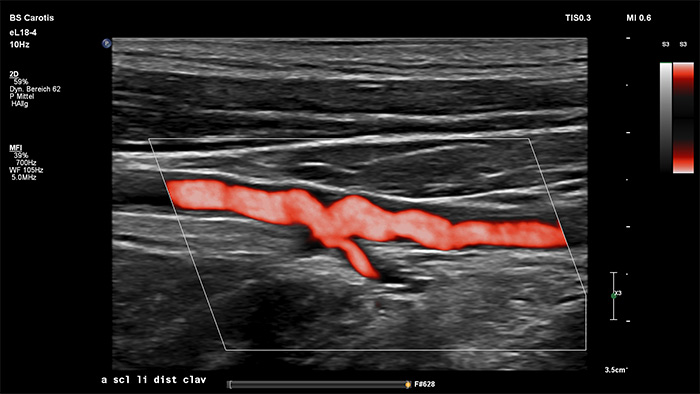

O MicroFlow Imaging da Philips foi concebido para detetar fluxo sanguíneo lento e fraco nas estruturas anatómicas do tecido com uma sensibilidade notável e melhorar a resolução do fluxo em exames vasculares. Com alta resolução e artefactos mínimos, os médicos podem visualizar e caracterizar perturbações subtis do fluxo à volta da placa estenótica para fazer diagnósticos confiantes.

The eL18-4 transducer is an ultra high-frequency linear transducer that incorporates ultra-broadband PureWave crystal technology with fine-elevation focusing capability, generating ultra-broadband frequencies from 2 to 22 MHz. The transducer’s advanced design allows for wide field-of-view trapezoid imaging and superb 2D detail resolution. It supports a broad range of high resolution applications including breast, small parts, vascular, pediatric and musculoskeletal imaging along with the penetration needed in obstetrical and gynecological examinations to help elevate clinical confidence.